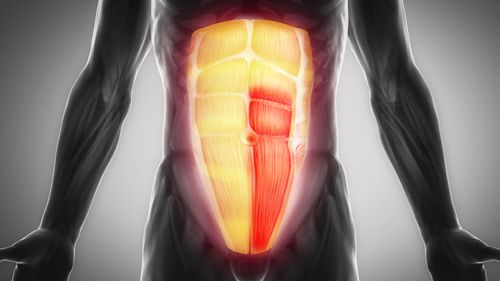

What Doctor To See For Abdominal Muscle Strain

What Doctor To See For Abdominal Muscle Strain

Abdominal Muscle Strain

Abdominal Muscle Strain How To Treat And Recover Abdominal Muscles

Abdominal Muscle Strain How To Treat And Recover Abdominal Muscles

Abdominal Muscle Strain Treatment Symptoms And Causes